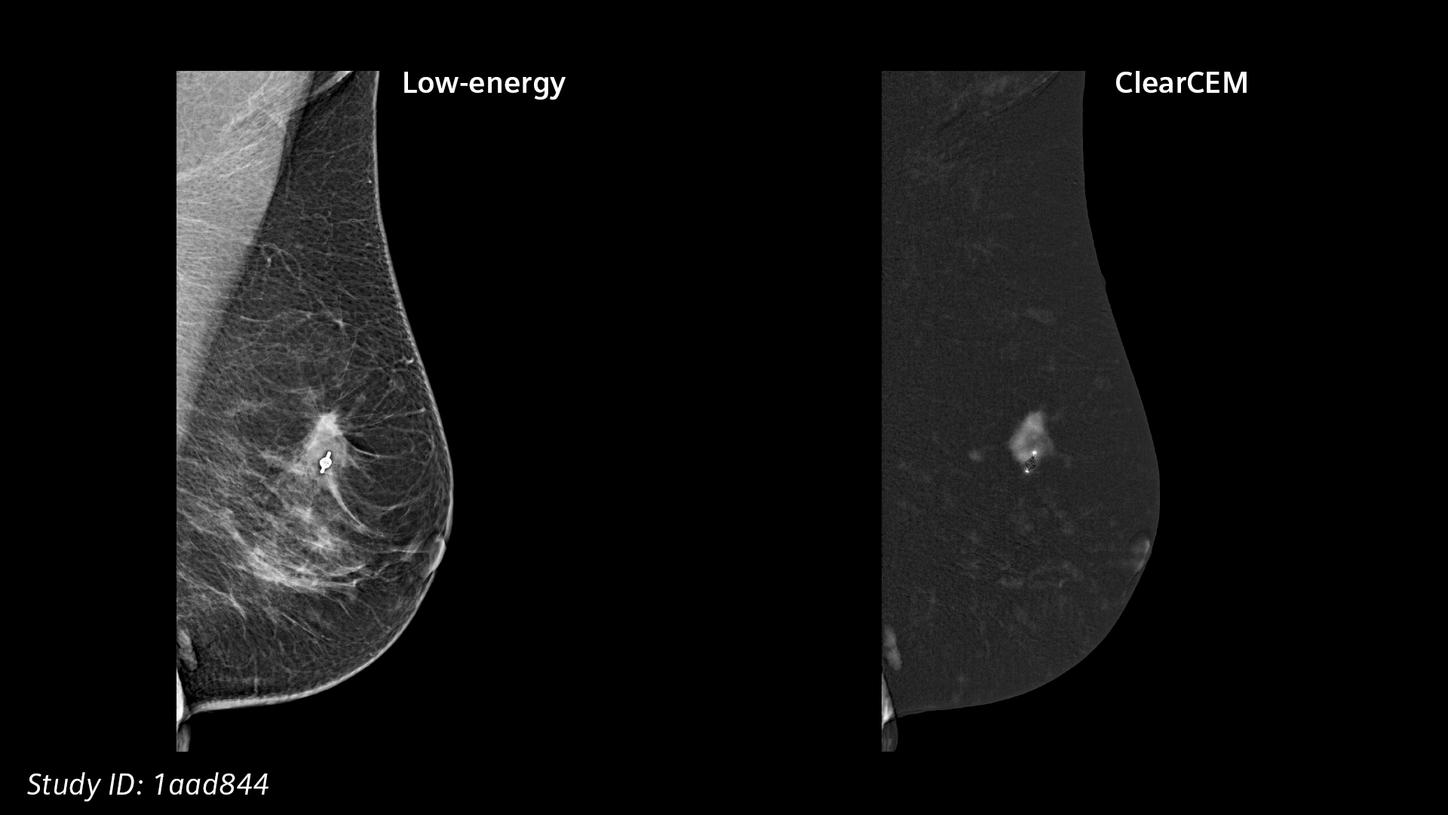

Our new recombination algorithm lifts CEM (contrast-enhanced mammography) breast imaging to a higher, brilliant level: with outstanding image quality, we are setting a new benchmark for accuracy and diagnostic certainty, bringing mammography closer to MRI.

ClearCEMA new era in contrast-enhanced mammography